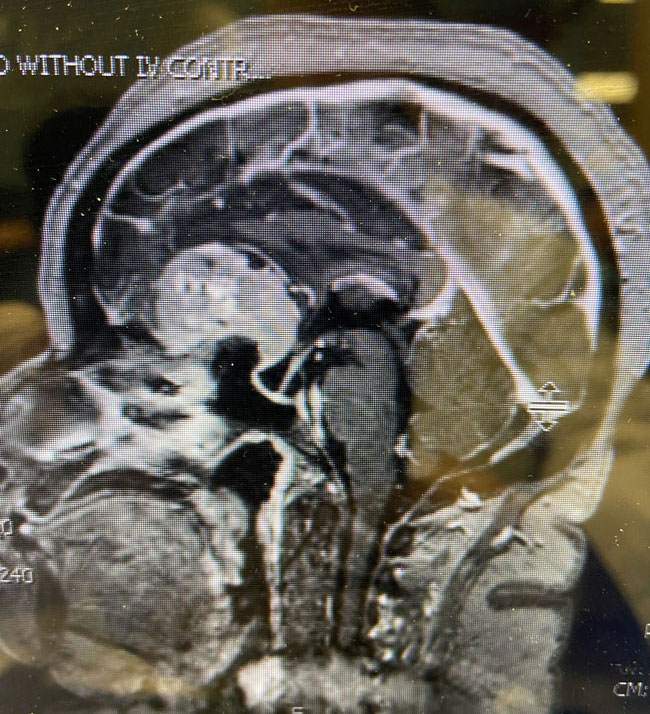

The patient underwent a bifrontal craniotomy and near total removal of the tumor. Because the frontal sinuses were small, it was possible to perform the craniotomy without violating the frontal sinuses. The tumor was removed nearly completely except for a small portion that was stuck to the optic nerves and the anterior communicating artery complex (Figure 2). Postoperatively, the patient immediately noted that her vision had been restored to normal. She was discharged on postoperative day 2. The small remaining tumor will be followed, and may be treated with stereotactic radiosurgery in the future.

Meningiomas can arise from any meningeal tissue within the brain or spinal canal. They are almost all benign tumors. This particular tumor arose from the planum sphenoidale, the flat posterior midline part of the sphenoid bone, a region that forms part of the floor of the anterior cranial fossa. Sometimes these tumors can be removed safely in entirety, depending on how adherent the tumor is to the deep surrounding structures, in particular, the optic nerves, the optic chiasm, and the anterior communicating artery. In this case, the tumor was quite adherent to these most posterior and inferior structures, so it was decided not to risk dissecting this last remaining piece of tumor off these critical structures.